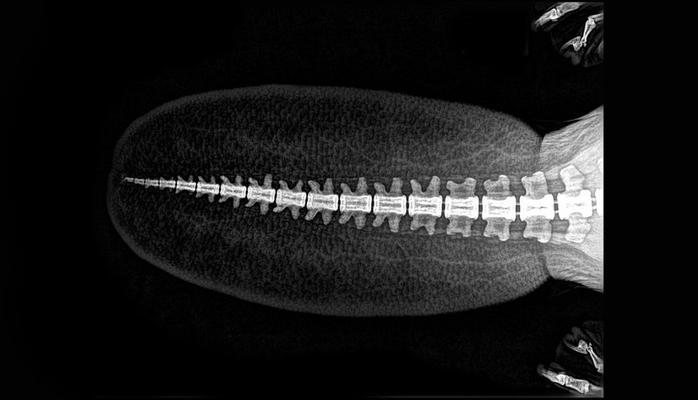

Piton